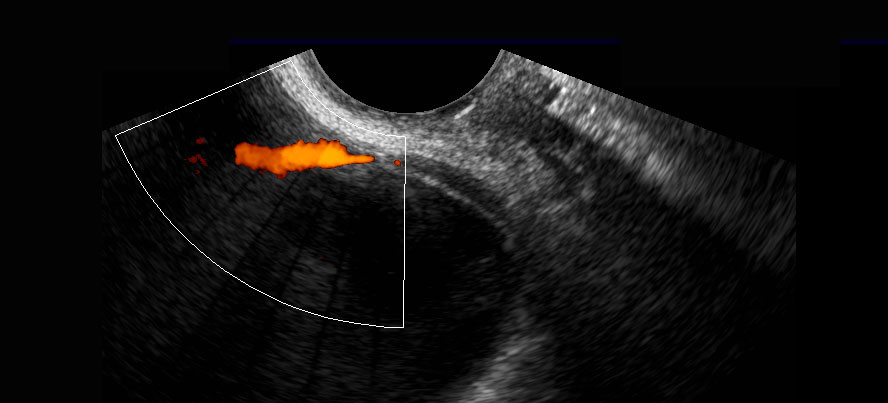

Siêu âm đầu dò âm đạo bổ sung cho thấy sỏi đoạn xa (mũi tên) trong niệu quản trái.